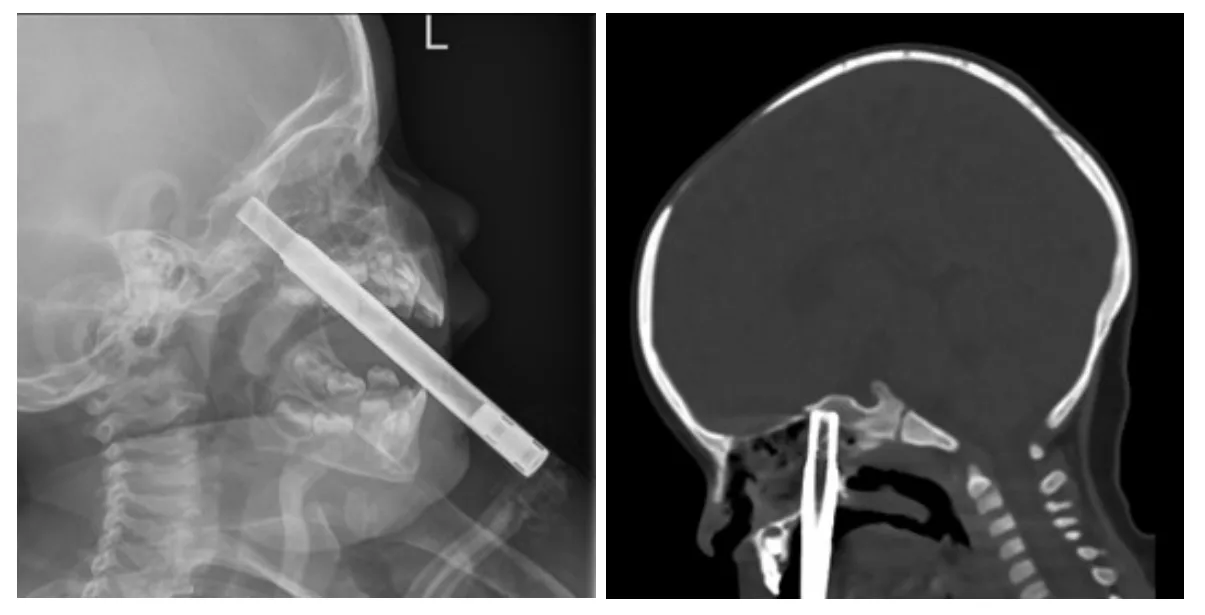

The X-ray showed the straw had pushed up into her nasal sinuses, “with the tip possibly sitting at the frontal skull base”.

Photo | New Zealand Medical Journal

A follow-up CT scan confirmed one end of the straw was lodged in the toddler's sphenoid bone, which sits right at the base of the cranium.